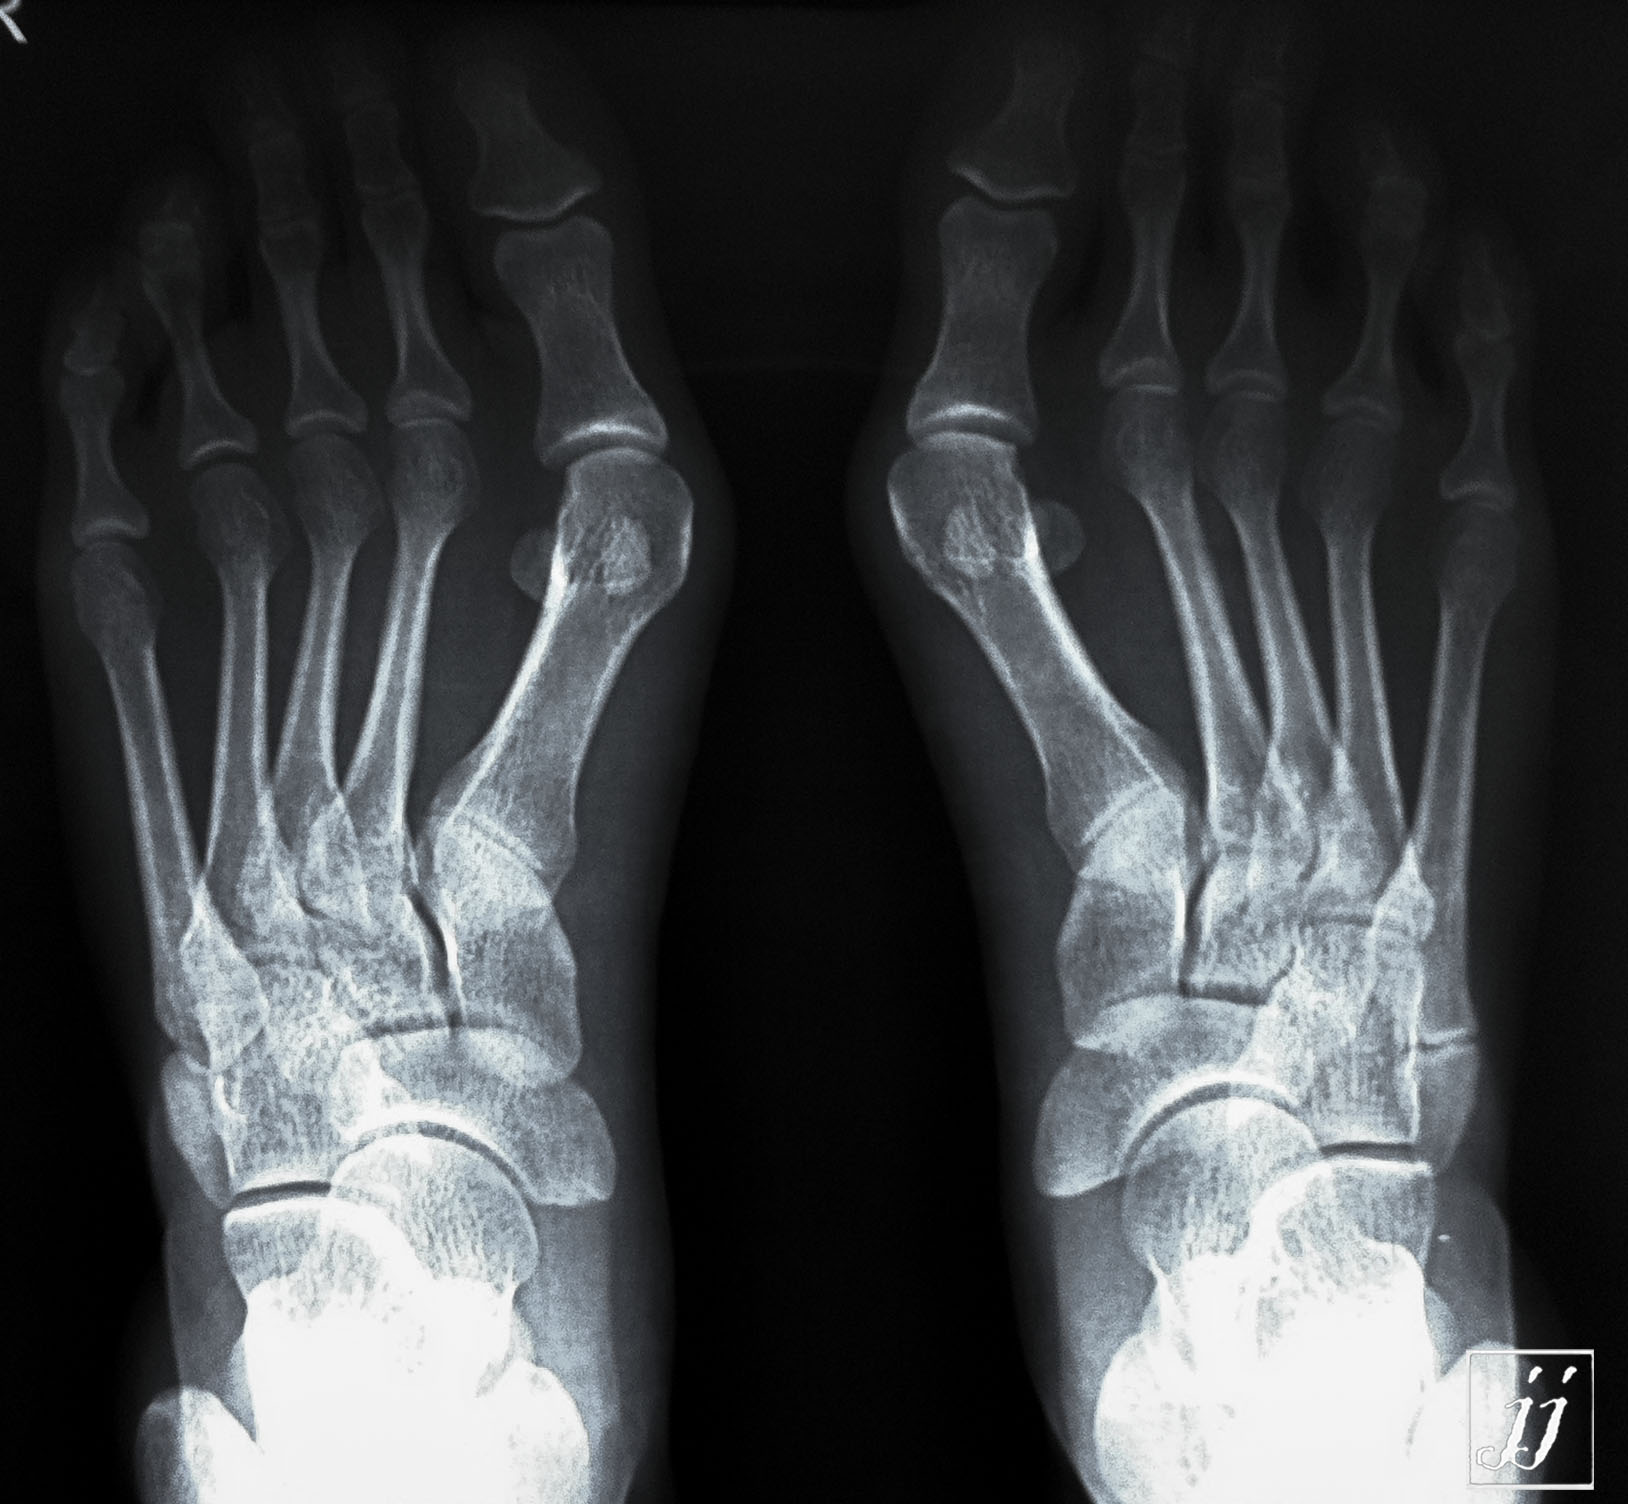

MSK- normal ankle joint (3)